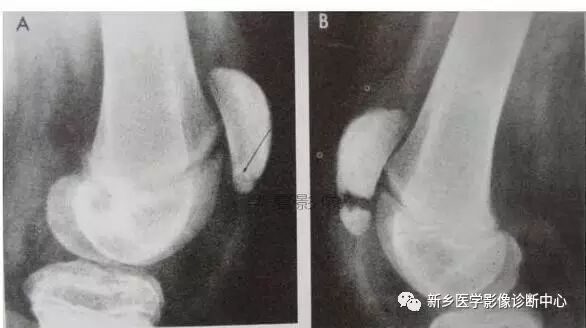

13、髌骨副骨化中心

• 髌骨副骨化中心之一(8Y男孩子)

• 髌骨副骨化中心之二(12Y男孩子,似骨折)

• 髌骨副骨化中心之三:

• 髌骨副骨化中心之四:

• 髌骨副骨化中心之五: